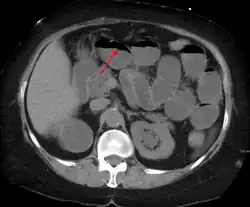

A small bowel obstruction as seen on CT